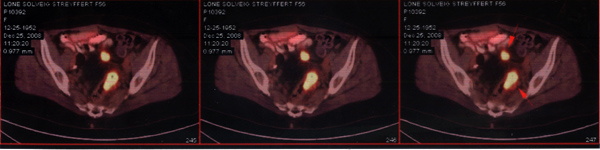

Sara小姐患卵巢癌,并发直肠转移癌、后腹膜腔淋巴结转移。PET-CT显示腹腔内多处有肿瘤活性。在新西兰共有5个医生为她治病,其中两位来自美国。由于以前她已接受卵巢切除,并做过全疗程化疗,因此进一步治疗遇到困难。2013年6月23日,Sara小姐来到广州中医药大学金沙洲医院。她接受了综合治疗:手术—>切除直肠肿瘤—>对残存肿瘤作WB-1无创全身热疗—>化疗。2013年9月28日出院。

Sara小姐治疗前CT